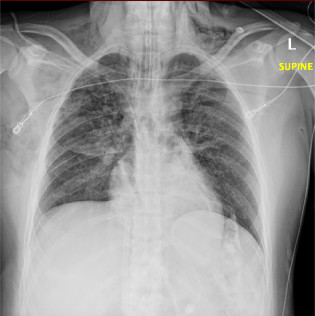

Next, we can look at the distribution of B lines across the thorax.

Note that this is why we always have to scan representative areas of BOTH sides of the chest - you cannot just take a single clip and call it pulmonary edemaβΌοΈ

B lines arising from pulmonary edema should be bilateral, symmetrical, and in a dependent gradient (ie. most prominent at the bases).

B lines from infectious/inflammatory pathologies, on the other hand, are often asymmetrical, non-gravitational, and may display skipped or spared areas.